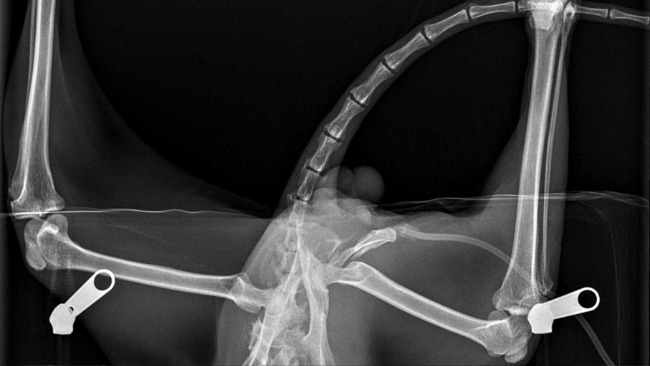

Od tygodni jeździmy z nim codziennie do weterynarza. I od tygodni obserwujemy, jak Desperado desperacko chce żyć. Nie może chodzić z powodu strzaskanej miednicy. Nie można było zdecydować się na operację, dopóki stan ogólny kota na to nie pozwalał.

A przed nim najważniejsza operacja: poskładania kości miednicy i nóg w całość. Operacja odbędzie się w całodobowej klinice. Operował naszego kota będzie doktor Krajewski. Wierzymy, że się uda i że w końcu Desperado stanie na nogi.